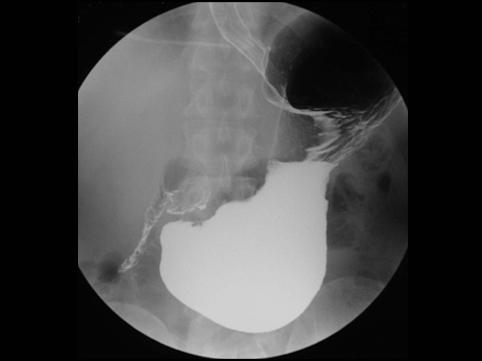

clasificación del pacienteTumor Epitelial Maligno/Cáncer a células en Sello de Anillo

parte(separada por órganos)estómago(región)/ángulo

método de exámenRayos X

clasificación ectoscópica de tumoresTipo 0(tipo superficial)/Tipo III(III+IIc)

diámetro mayor del tumor10 - 14

grado de penetraciónsm